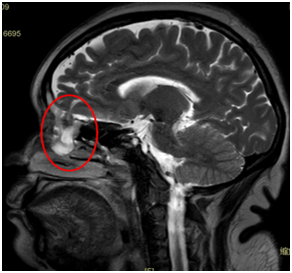

手术后

医生从她的蝶窦里

取出了10多个真菌团

每个都有黄豆大小